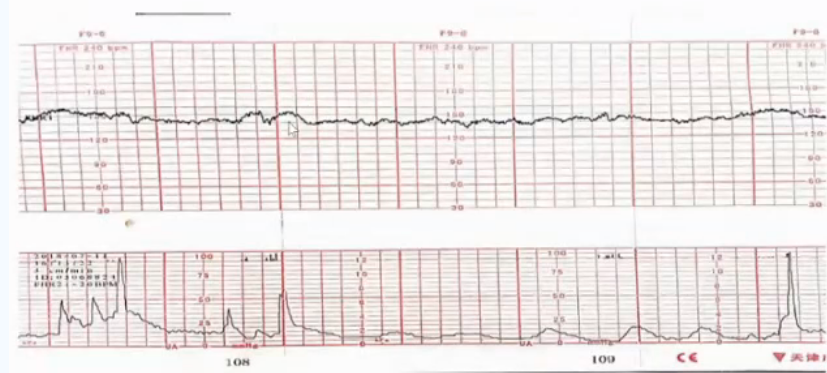

穿戴式胎心监护是基于电生理技术原理设计的外监护设备,弥补了多普勒探头和宫腔压力探头操作复杂、笨重和易受体位干扰的不足。通过贴附于孕妇腹部的穿戴式监测传感器,动态捕获母胎心电信号和子宫肌电信号,经计算机实时处理后描记形成胎心监护图形。这种技术可以避免胎儿心率和母体心率的混淆,有效解决胎心率断线、加倍、减半的问题,适合高危妊娠和胎心监护图形异常孕妇进行长时间连续监护[1]。

穿戴式胎心监护

由于多普勒胎心率探头可能受到母体腹主动脉搏动信号的干扰,为了避免设备将母体心率误读为胎儿心率,可考虑采用如下方案[3]:①同步监测母体心率,并绘制母体心率曲线;②采用穿戴式一体化胎心监护设备,尤其是肥胖或腹壁过度松弛的孕妇,基于心电信号技术的胎心监护设备可以提高监护效率,无需反复调整探头位置[6-8]。

穿戴式一体化胎心监护